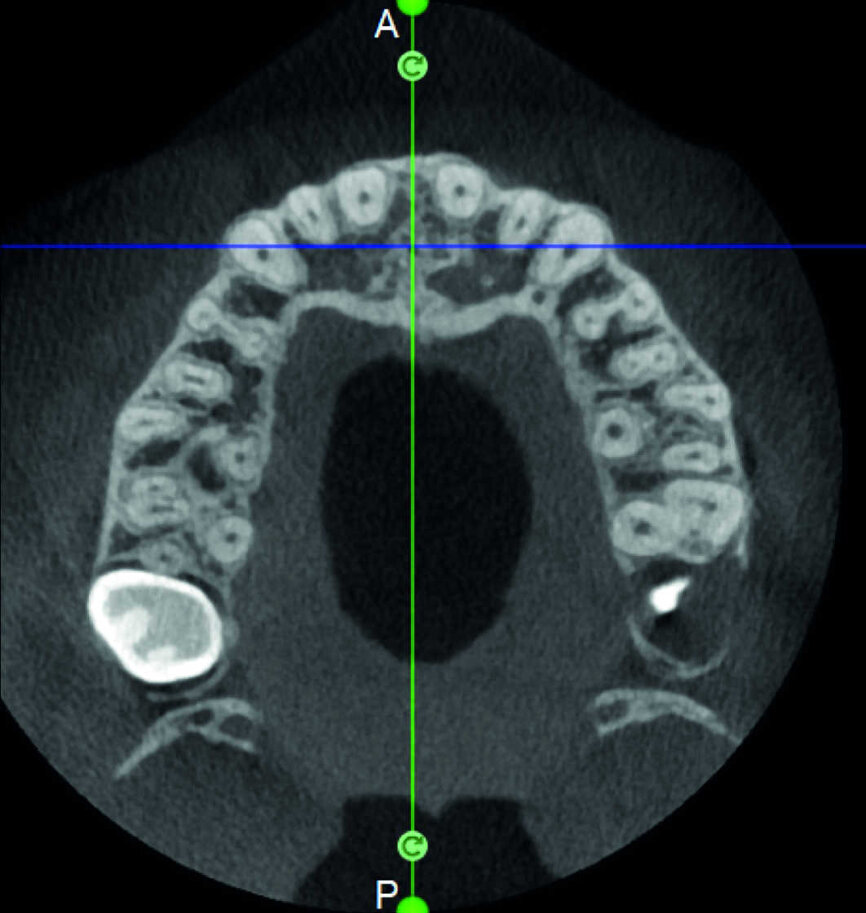

Le cas avec lequel je souhaite commencer mon exposé clinique est un exemple parfait de la difficulté à définir l’origine des symptômes d’un patient, par l’examen d’une simple radiographie intraorale. Non seulement l’examen 2D ne permet pas d’établir avec certitude la présence d’une lésion, mais surtout, il est impossible d’en déterminer la taille, la morphologie et le type. Au contraire, une analyse de l’imagerie 3D offre une image claire de la situation clinique. Chez ce patient, les coupes coronales et sagittales révèlent la présence d’une importante lésion s’étendant de l’apex de la racine mésiale de cette molaire jusqu’à la zone de furcation, tandis que les coupes axiales nous permettent d’analyser précisément l’anatomie endodontique et, en particulier, la forme de la racine mésiale, qui apparaît fusionnée avec la racine palatine. Un panorama complet du cas peut donc guider le processus de décision et orienter le plan de traitement vers une modalité bien précise de traitement (Figs. 1–4).